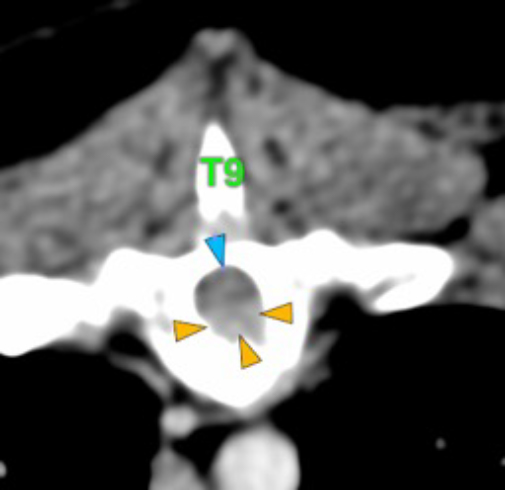

The osteolytic lesions have soft tissue attenuation that shows moderate and slightly heterogeneous post-contrast enhancement. In some of the vertebrae, the lesions cause lysis of the cortex and extend into the vertebral canal (orange arrows) causing variable degree of compression of the spinal cord and cauda equina (blue arrows). At the level of the vertebral bodies of T7, T8, T9 and T12 the lesions extend into the ventral and central aspect of the vertebral canal causing a mild compression of the spinal cord. At the level of T13, L1, L4 and L5 the lesions extend into the ventral and central aspect of the vertebral canal, causing moderate compression of the spinal cord. At the vertebral body of L6 the lesion extends into the ventral and central aspect of the vertebral canal, at the mid-aspect of L6, occupying approx. 90% of the diameter of the vertebral canal causing a severe compression of the cauda equina. At the level of L7, the lesion extends into the ventral and both lateral aspects of the vertebral canal, causing severe compression of the cauda equina.